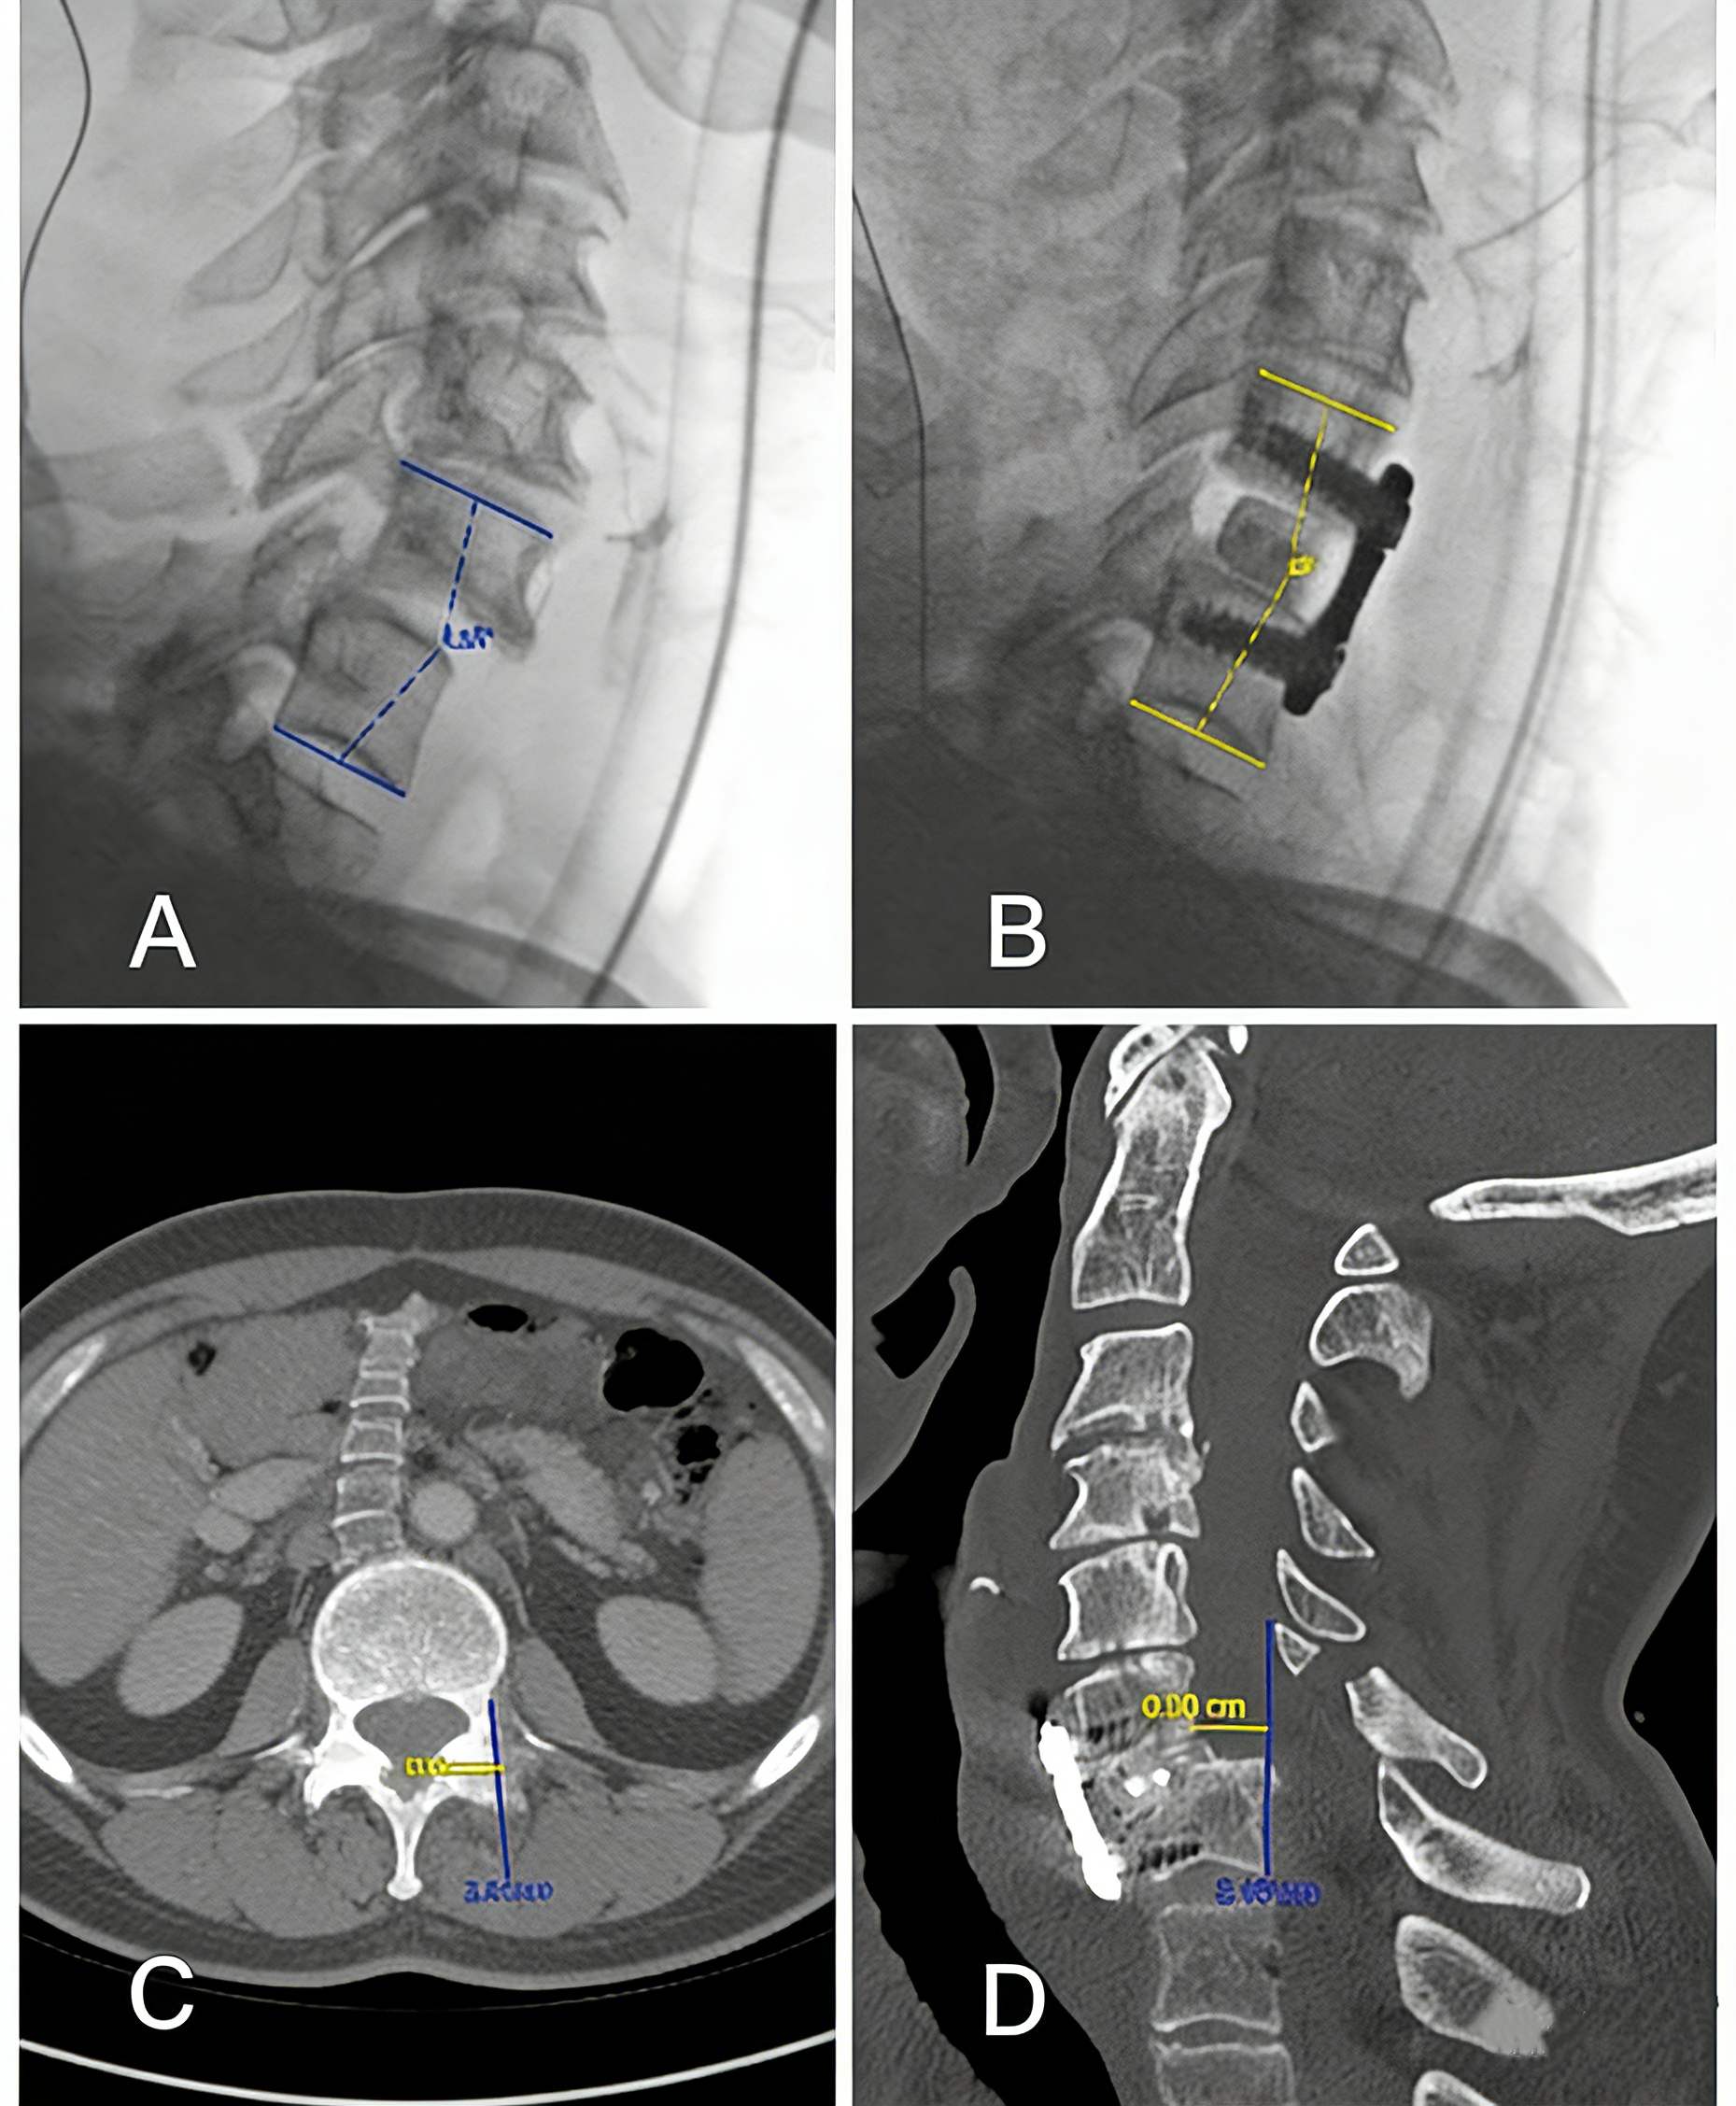

3_副本.jpg

Pre- and post-anterior ACDF internal fixation imaging.